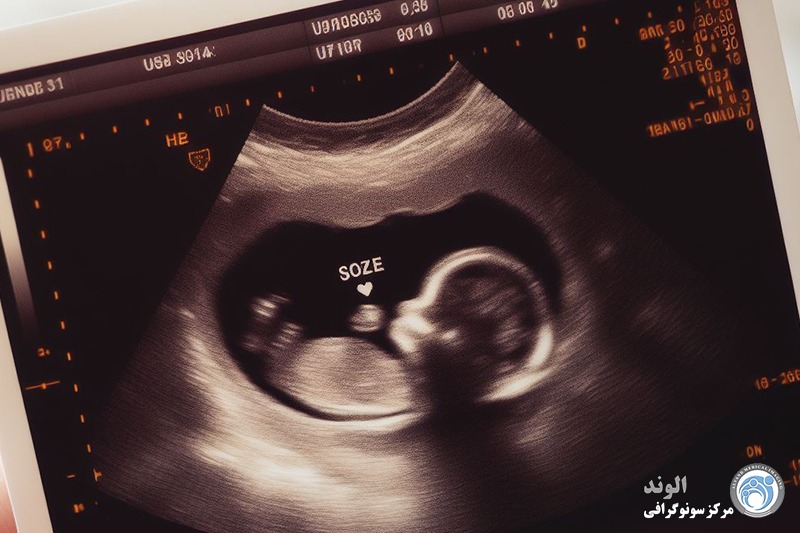

تعداد جنین ها و در نتیجه اینکه آیا ما دوقلو خواهیم داشت یا چرا که نه، سه قلو! همچنین به طور دقیق تاریخ لقاح کودک را تعیین می کند، که برای نظارت بر رشد آن و عدم خطر فراتر از دوره بارداری ضروری است.

نشاط نوزاد: سونوگرافیک فعالیت جنین را در صورت متحرک بودن و زیاد بودن حرکات مشاهده می کند.

مورفولوژی نوزاد: پزشک مطمئن می شود که هیچ گونه ناهنجاری مورفولوژیکی وجود ندارد. جمجمهاش را معاینه میکند، بررسی میکند که دو دست و دو پا دارد و هر یک از اندامهایش بهخوبی به ۳ قسمت (ساعد، بازو، دست) تقسیم شدهاند که قلبش در سمت چپ است. همچنین توجه می کند که دیواره قدامی شکم به خوبی بسته باشد، معده و مثانه در جای خود قرار گیرند. او نگاه می کند تا ببیند آیا ستون مهره (ستون فقرات) هیچ گونه ناهنجاری را نشان نمی دهد... توجه ویژه ای نیز به محیطی که نوزاد در آن زندگی می کند معطوف می شود: میزان مایع آمنیوتیک، مطالعه و محل جفت.